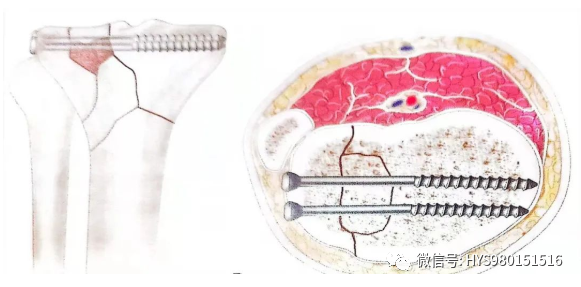

• 直视及透视下观察骨折复位情况,然后用螺钉和带螺纹的细针固定较小的骨折块。

• 固定材料平行于关节面并尽量接近关节面,并且没有穿透关节面,给环形外固定架保留足够的空间。

什么是外固定架胫骨近端骨折:环形外固定架_https://www.jmylbn.com_新闻资讯_第21张

▲ 示意图

• 内外侧平台在同一平面,不能在不同平面。

什么是外固定架胫骨近端骨折:环形外固定架_https://www.jmylbn.com_新闻资讯_第22张

• 内外侧平台在同一高度,不能在不同高度。